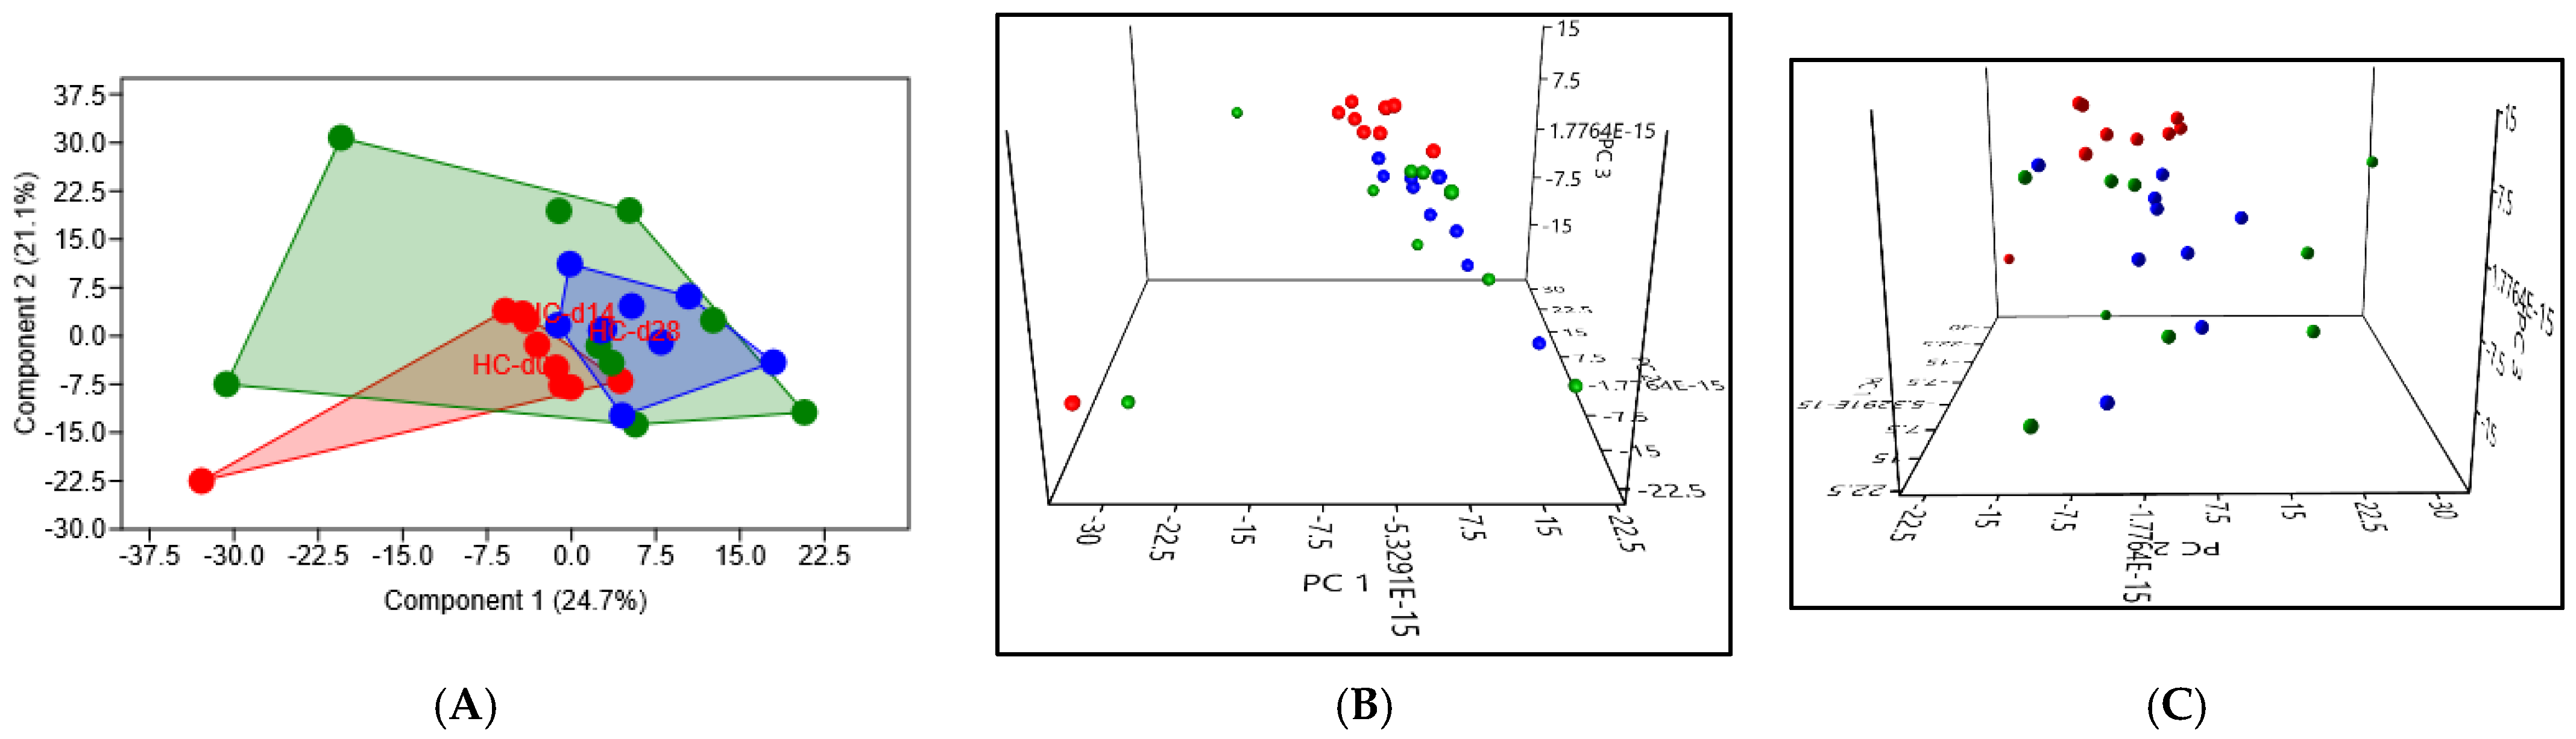

3.3.2. Beta Diversity